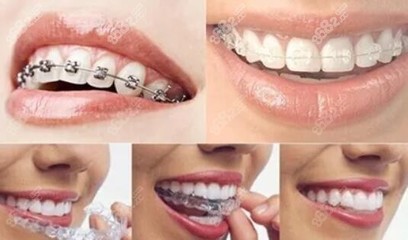

正畸过程可以分为这几个阶段:1。咨询:包括治疗前的临床检查、诊断资料的收集(如石膏模型、面部外观及口腔牙列摄影、面部及牙列X线检查等。),对病历的诊断分析,治疗方案的制定,对患者的讲解和讨论。2.开始正畸治疗:治疗方案确定后,医生会根据患者的病情和要求选择合适的托槽,并进行相应的调试、粘接和施力。正畸治疗首先从牙齿的治疗开始,然后一般每个月就诊一次。具体时间由医生根据治疗需要决定,每次就诊时会做必要的检查和记录。